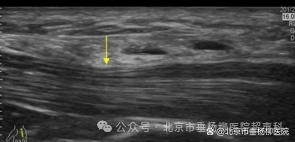

➭ 超声引导:在超声影像的实时监控下,医生将治疗器械(如注射针头)精确地插入病变部位。超声波提供的实时动态影像,使医生能够清晰地观察到治疗器械的位置和周围的组织结构。